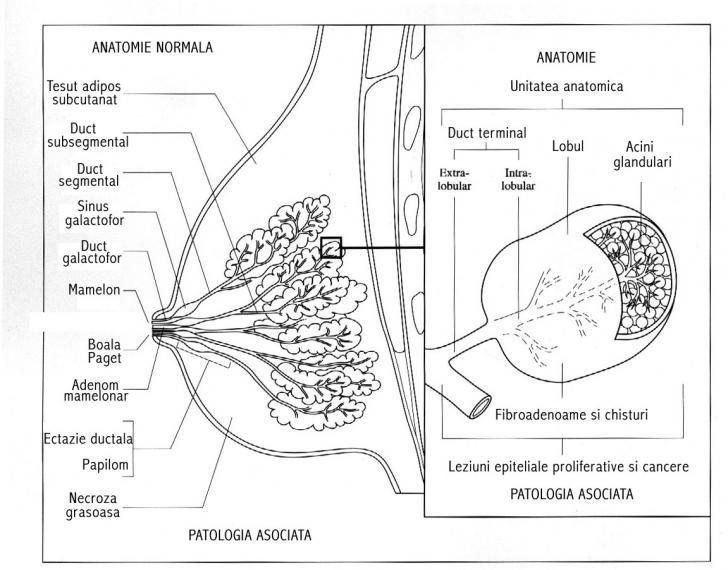

MAMECTOMII SECTORIALE - CHIRURGIE

MAMECTOMII SECTORIALE - CHIRURGIE I. DEFINITIE Mamectomia sectoriala reprezinta interventia prin care se realizeaza extirparea unei portiuni din glanda mamara. Termenul de mastectomie partiala cuprinde mai multe variante de excizie: lumpeCiteste tot ... 2083 cuvinte